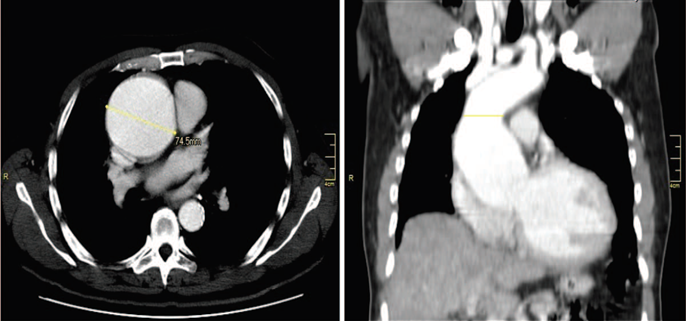

A 61-year-old male with a history of dyslipidemia and high arterial blood pressure (ABP) being managed with enalapril 10mg/day and carvedilol 3125mg/day. He presented a clinical record of 2 months of evolution of occasional episodes of puncture-type chest pain associated with palpitations that spontaneously gave way. He was diagnosed with ascending aortic aneurysm and severe aortic insufficiency, requiring cardiovascular surgery. However, he manifested he was a Jehovah's Witness and did not accept transfusions. Pre-operative optimization was initiated with Erythropoietin 280U/kg weekly, ferrous sulfate 200 mg/day, folic acid 1000 μg/day reaching a hemoglobin (Hb) level of 11 to 14.6 g/dL. He consulted the emergency room with 2 hours of sudden pain in the left hemithorax irradiated to the ipsilateral axilla, associated with dyspnea, coldness and paresthesia in the hands. His ABP was 122/35 mm Hg, heart rate (HR) 58bpm, respiratory rate 18/minutes, arterial oxygen saturation 98%, diastolic heart murmur grade IV/IV in aortic focus without other relevant findings. Transthoracic echocardiogram showing severely dilated left cavities, eccentric left ventricular hypertrophy, left ventricular ejection fraction 41%, tricuspid aortic valve with severe insufficiency (AI), mild mitral insufficiency, annuloaortic ectasia (52 mm aortic root, 71 mm ascending aorta). Thoracic aortogram evidenced severe dilation of the sinuses of valsalva and ascending aorta with a diameter of 70.9 mm (Fig. 1).